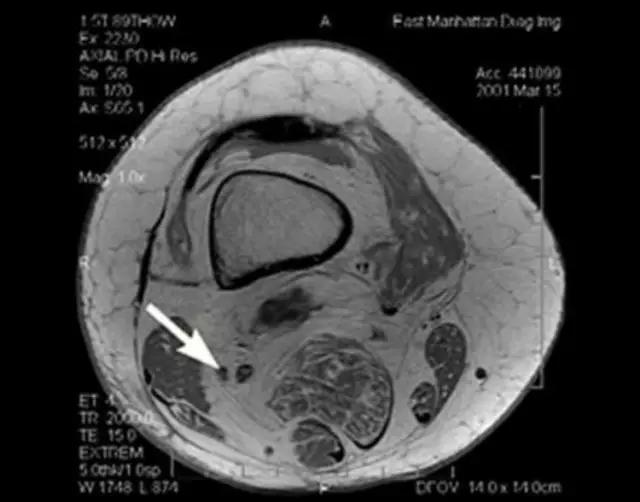

利用自身对比——

我们可能都不熟悉T1、T2,怎么办?当我们发现有问题后,利用照片上图像的对比,推测病变的可能也是一种诊断方法。病例:黄XX,女,39岁,左膝关节反复交锁1年。图1:肿物信号与骨信号一样图2:肿物信号与骨信号一样图3:肿物信号与骨信号不一样 肿物应该与骨相关,但不是骨性,推断:膝关节滑膜软骨瘤。手术后得到证实。